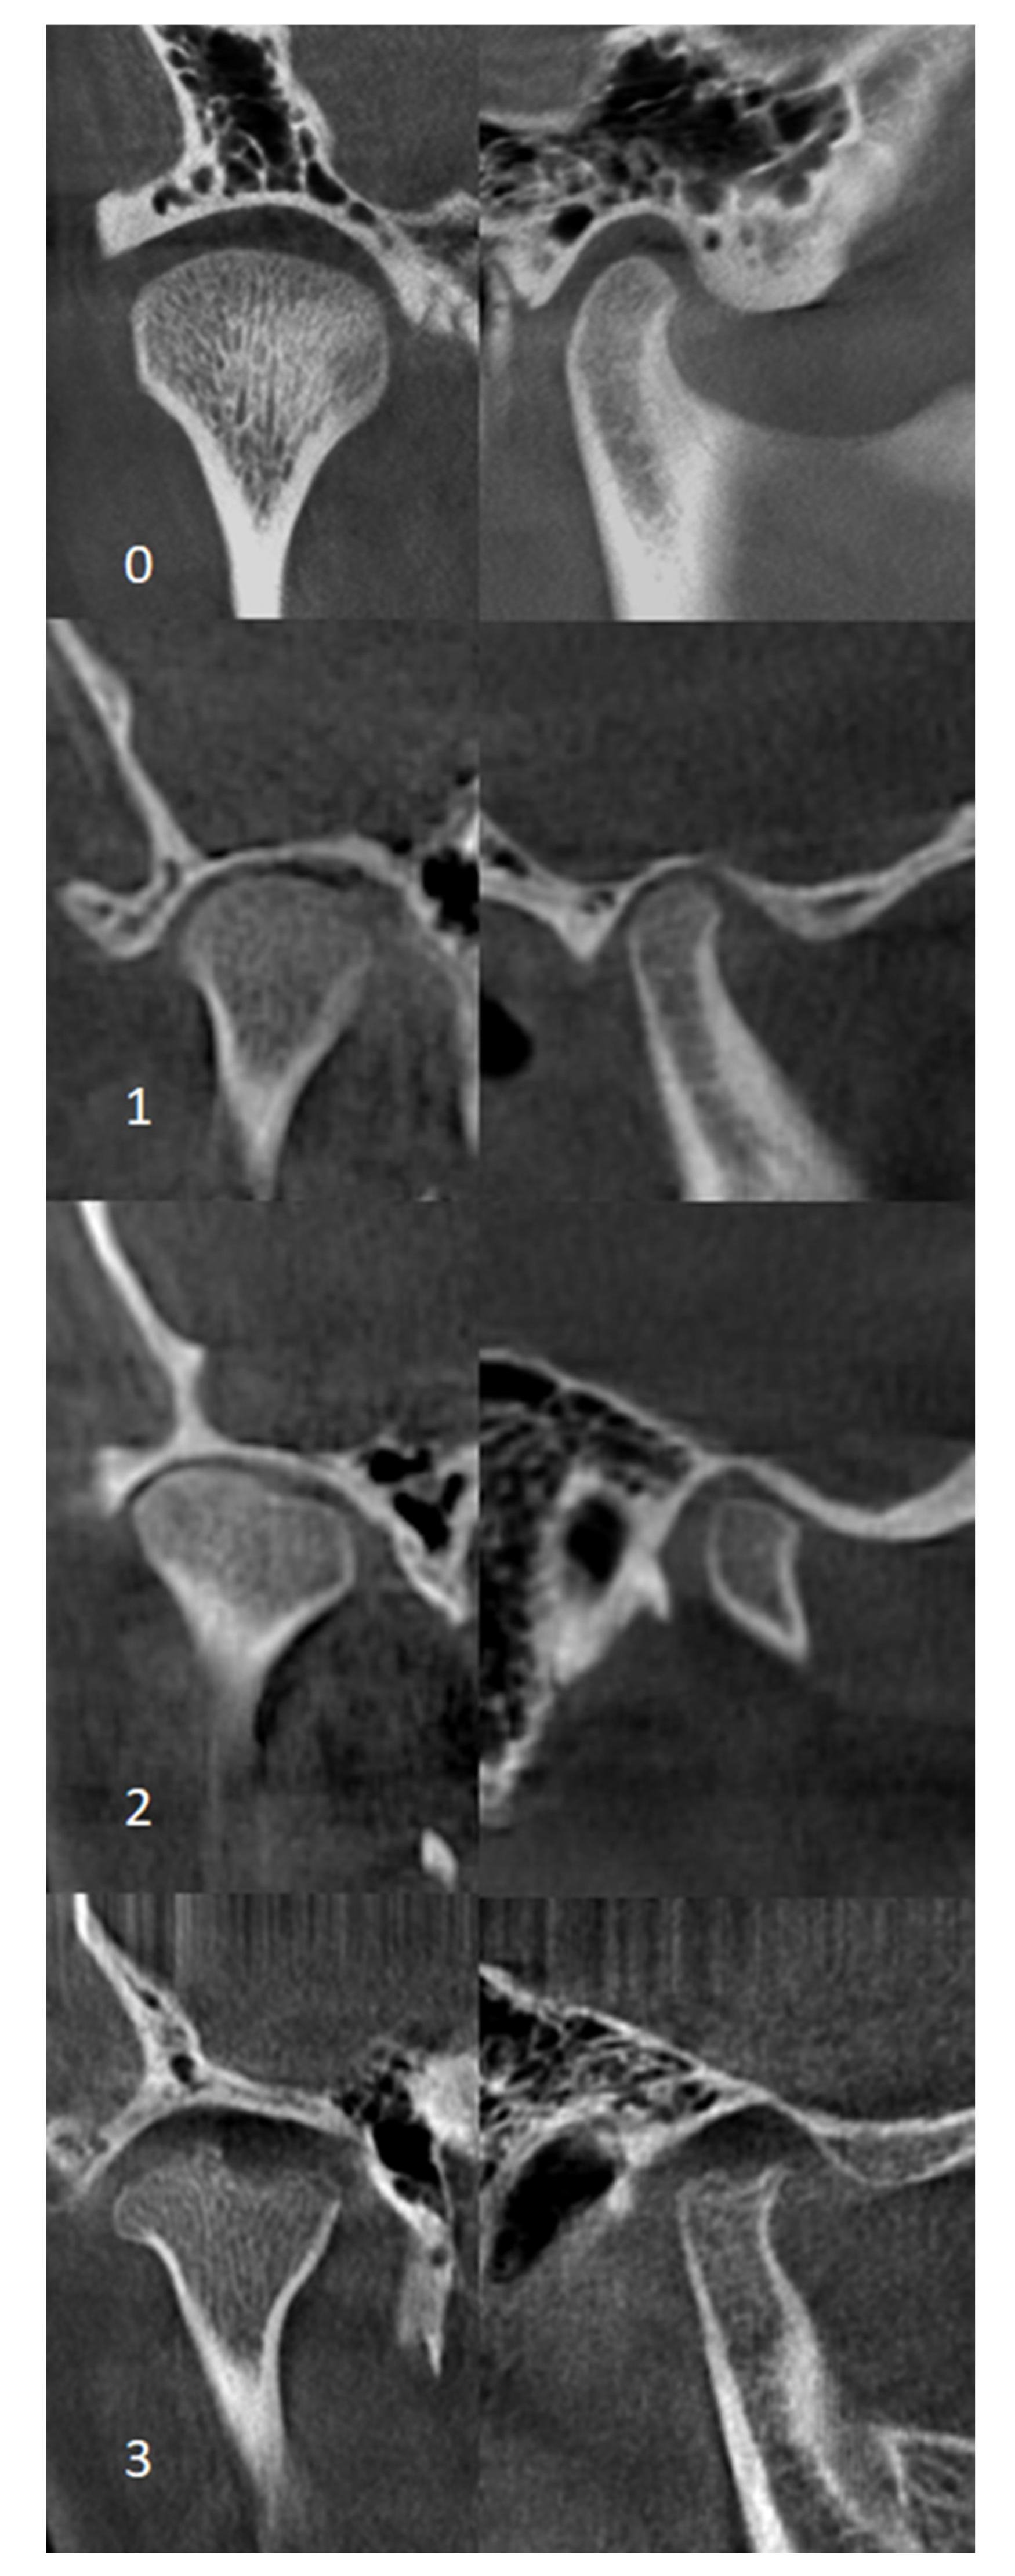

2.6. CBCT Examination